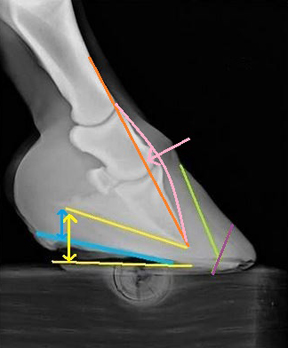

The hoof in Photo 4 demonstrates both bony and capsular rotation. In a healthy foot, the palmar angle, or back of the coffin bone (yellow arrow), usually sits at about 5 degrees (+/-) to the ground. The bony column is aligned (orange), with no knuckling forward (pink) or dipping back. By lowering the heels to the blue line, another fundamental aspect of a realigning trim with bony rotation, the bones will be "derotated" (pink arrow) and the palmer angle returned to about 5 degrees (blue arrow). It usually happens as quickly as that.

The capsular rotation can be addressed by backing up the toe to rid the foot of the toe flare (purple line).